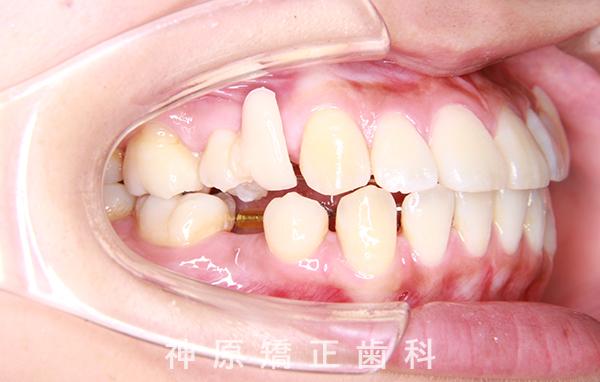

- 前歯が出ている

初診時

治療前と治療後

今回の矯正治療にあたり、矯正精密検査の結果をもとに診断を行いました。その結果、左下の永久歯が生まれつき欠損していました。歯並びの乱れや口元の突出感を改善するため、小臼歯と残っている乳歯を抜くことが必要だと判断しました。